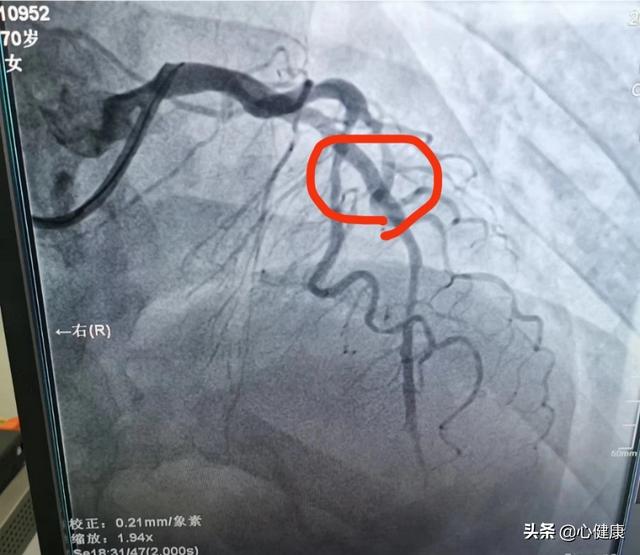

前下行枝の閉塞は通常、急性心筋梗塞の結果として起こり、患者は胸部圧迫感、胸痛、冷や汗を経験する。胸痛は通常長時間続き、緩和されない。心筋酵素は上昇し、冠動脈造影では前下行枝の100%の狭窄が認められる。この場合、血管が閉塞して血流が遮断され、血液がうまく供給されなくなる。これが心筋壊死につながる。患者によっては、側副血行路が充実しているため、それほど強く感じない人もいる。

血管が閉塞した場合、血液はどのように供給されるのでしょうか?いくつかのシナリオが考えられます。ひとつは心筋梗塞のように、血管が閉塞した後に血流が遮断され、それがそのまま遠位端への血液供給不足につながり、血液が供給されないまま心筋が壊死して悲劇を招くケースである。ある場合には、閉塞した血管がそれ自身の側副血行路を確立し、微小血管を通じて少量の血液供給を行うことができる。もう一つの状況は、他の血管を通して側副橋を確立し、虚血や低酸素状態の心筋に血液を供給することである。